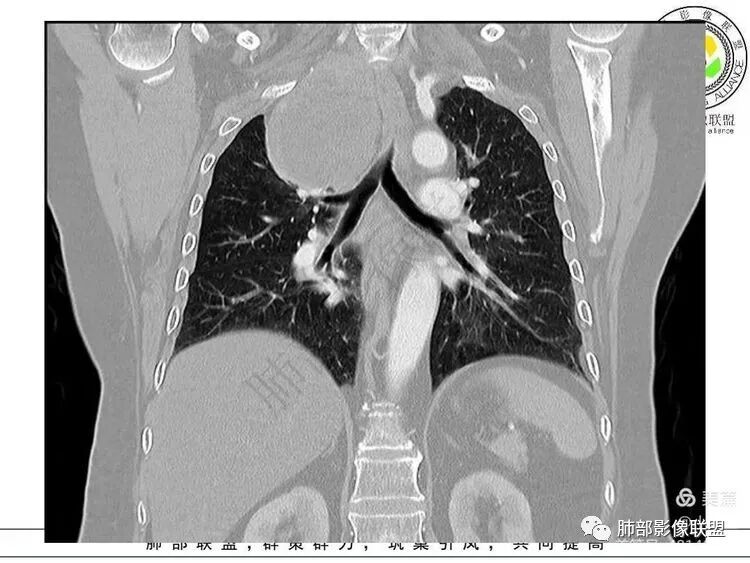

南边:支持:神经源性,从病灶的形态突入颈部,跨多区域

从病灶的形态看:前外侧肋骨区域没有推开,纵隔侧没有受限迹象,提示病灶欺软怕硬,朝薄弱的地方发展。

胸膜来源?应该肺侧最薄弱,朝肺内突最明显

而不应该朝最硬的颈部凸起

支持纵隔来源,神经源性肿瘤,胸膜来源SFT其次,异位再次

2.肿块远离胸膜向上延伸不大符合胸膜来源的孤立性纤维瘤。

3.而“A/B”区密度特点以及上下径较大更支持神经鞘瘤,尽管这不属于好发部位。